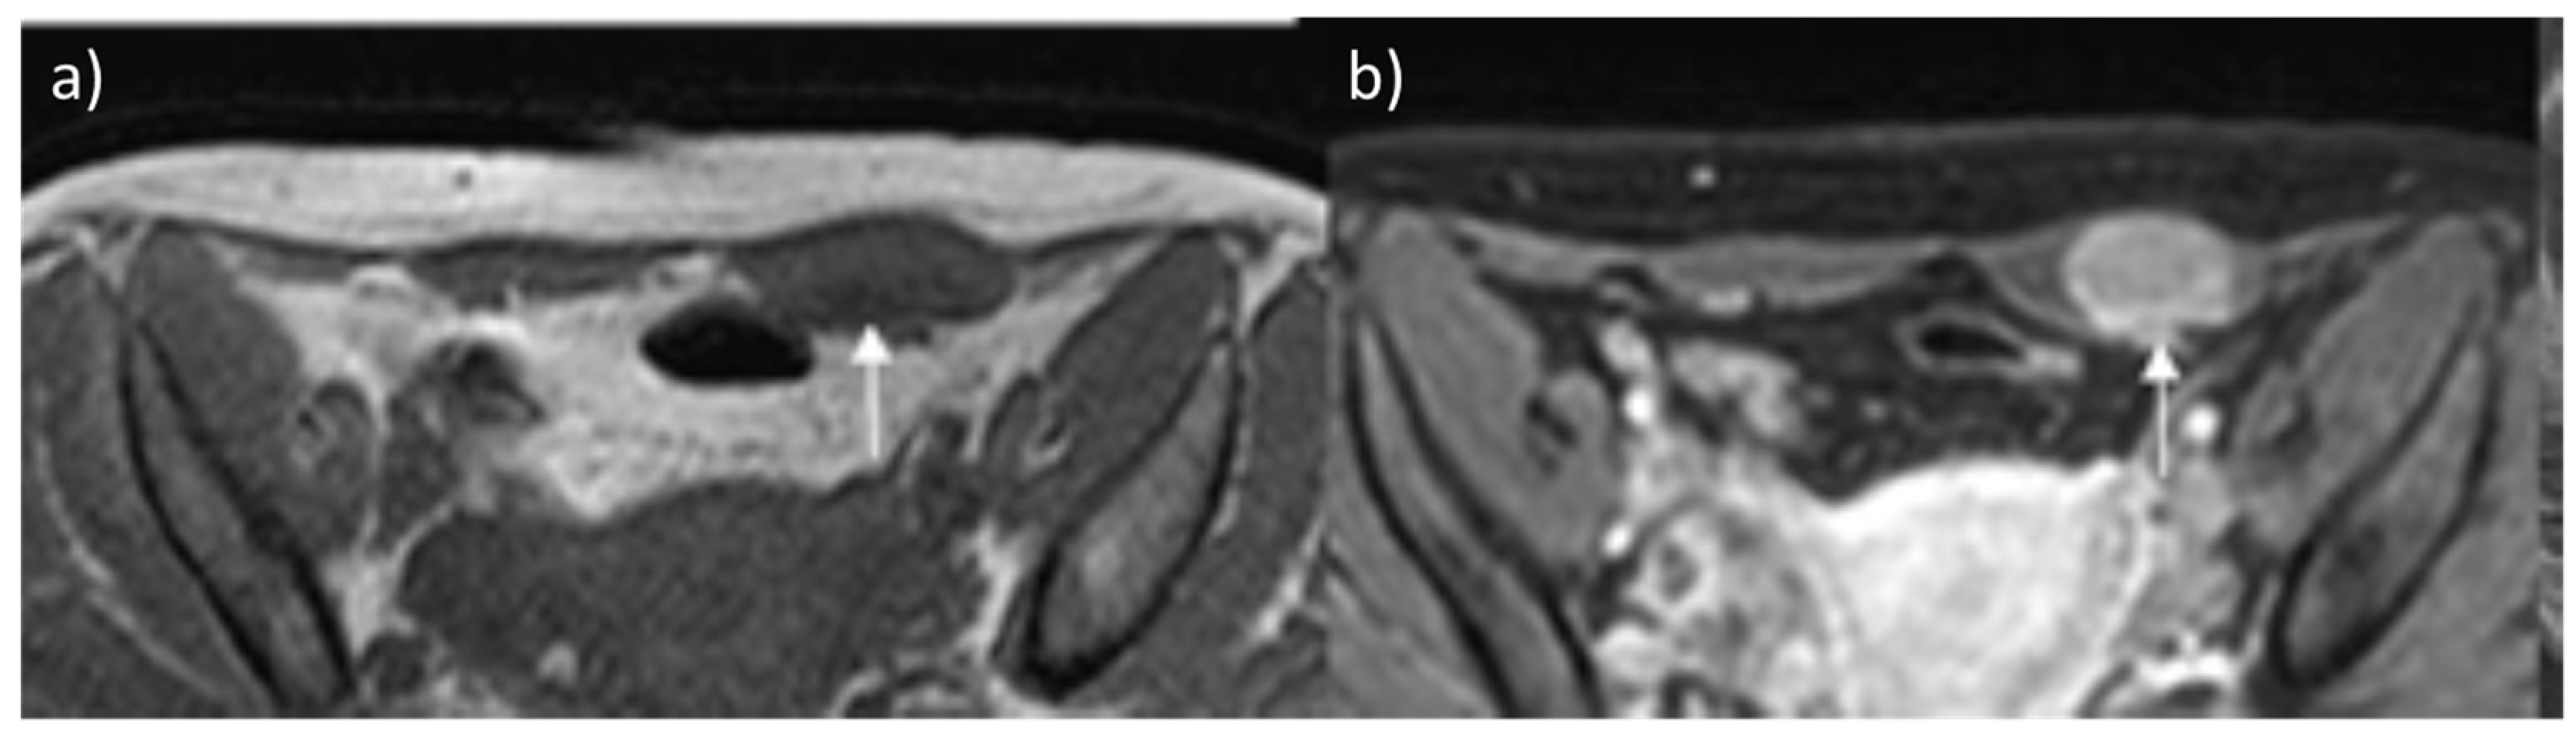

2.3. Hemangioma